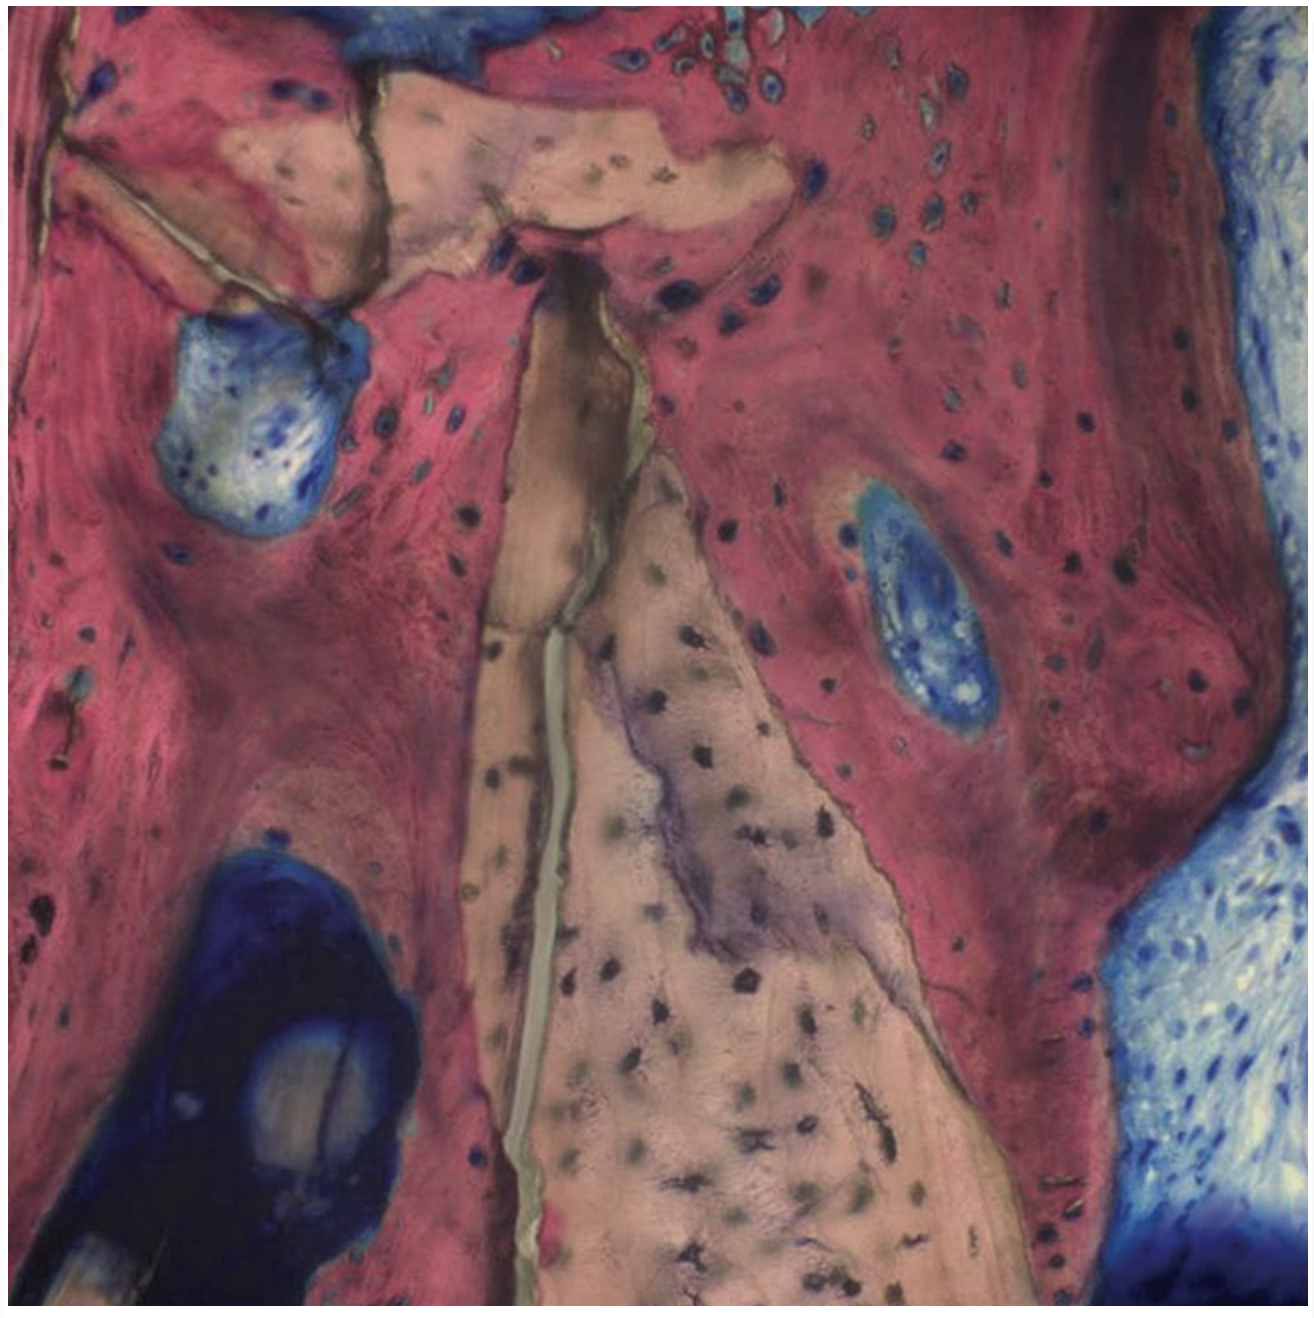

Figure 16  Histomorphometric analysis revealed 100% vital bone.

Figure 16

A 62-year-old woman was referred for fixed tooth replacement of the missing maxillary left cuspid, bicuspids, and first molar (Figure 11). Clinical and CBCT evaluation revealed an almost fully pneumatized maxillary left sinus along with alveolar width deficiency. The treatment plan called for a four-unit, implant-supported splinted fixed bridge. A left sinus augmentation along with a ridge split and interpositional bone graft consisting of rhBMP-2/ACS (INFUSE Bone Graft) and mineralized allograft (MinerOss) covered by a dense porous polyethylene mesh (Medpor®, Stryker, www.stryker.com) were done simultaneously (Figure 12, Figure 13 and Figure 14). Six months later, a follow-up CBCT revealed a well-incorporated graft with adequate bone volume and density for implant placement (Figure 15 and Figure 16). Final bridge fabrication followed 3 months later (Figure 17 and Figure 18).